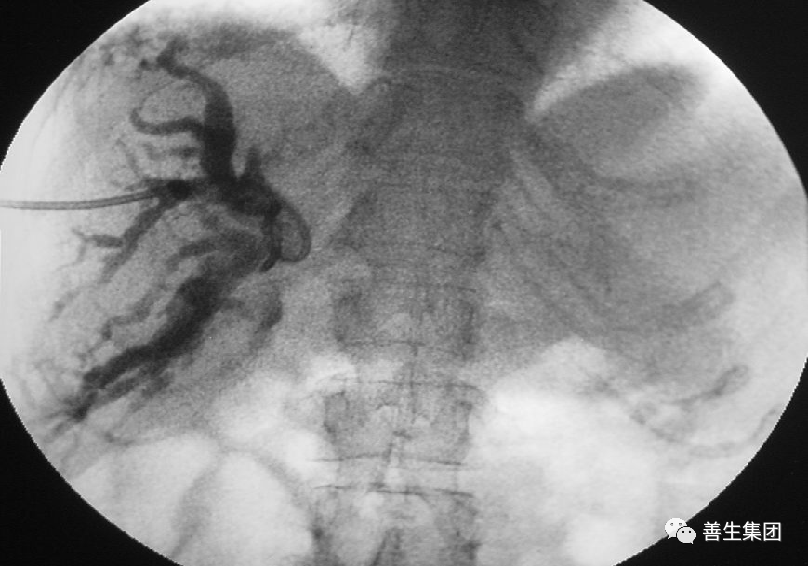

高位梗阻PTC示肝门部梗阻,左右肝管分别受侵犯

胆管支架什么样子经皮肝胆管穿刺置管引流术(PTCD)及胆道内支架临床应用_https://www.jmylbn.com_新闻资讯_第9张

高位梗阻胆管癌患者